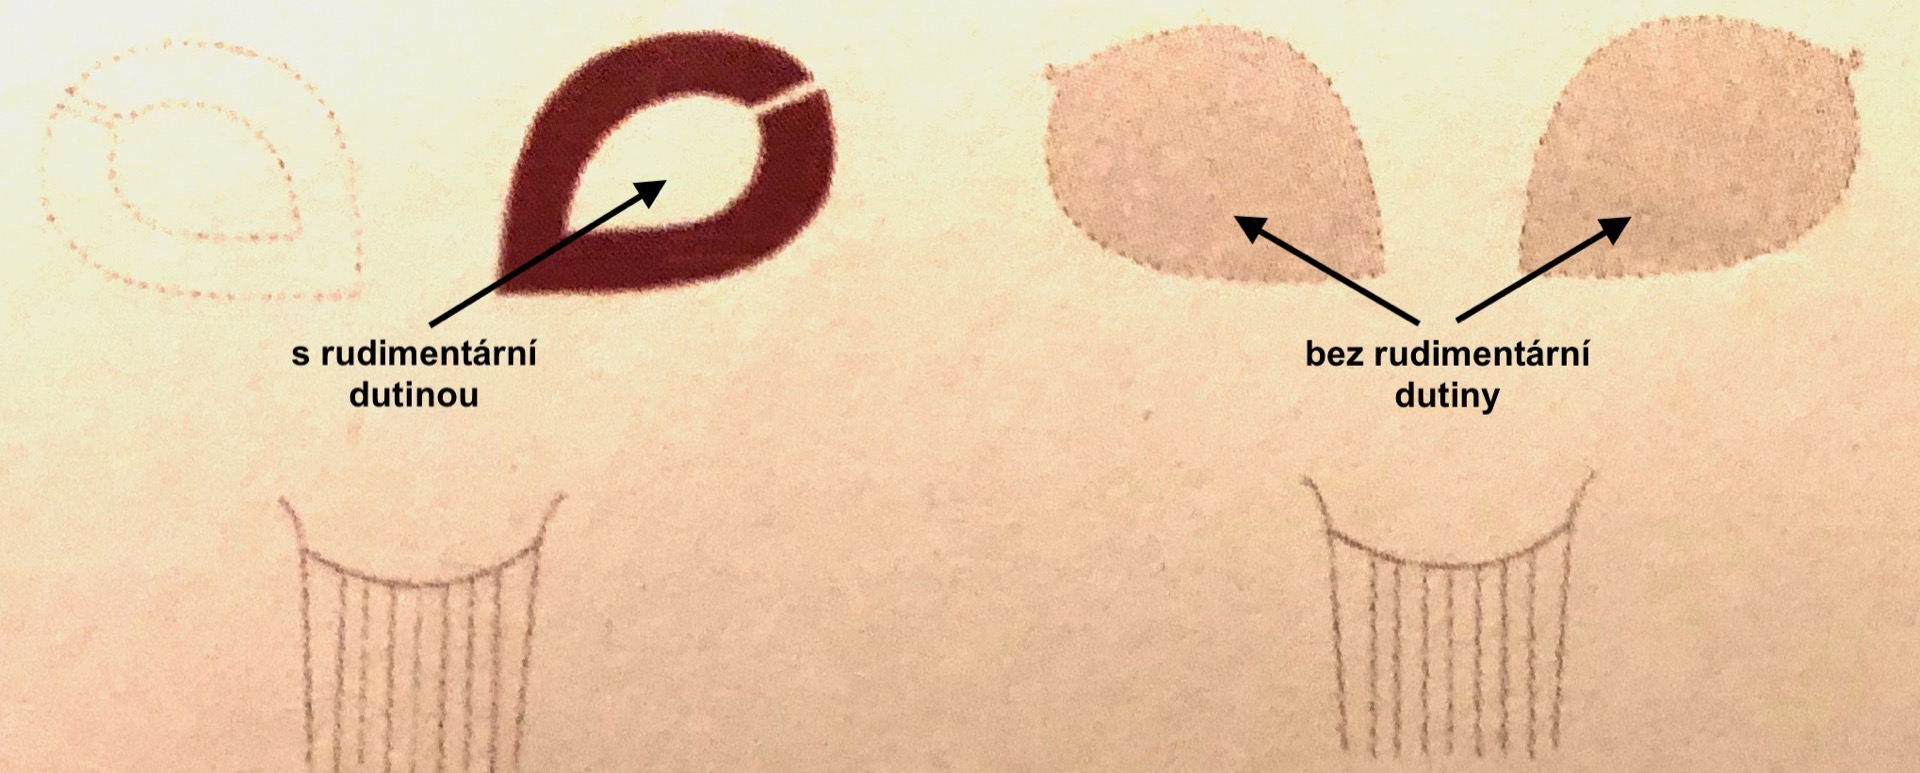

- Děloha vytvořená pouze z jednoho Müllerova vývodu. Část tvořená druhým Müllerovým vývodem je neúplně vyvinutá (rudimentární) nebo chybí-hemi uterus (dřívejší název uterus cum cornu rudimentario nebo uterus unicornis). Pro zapamatování tohoto druhu vývojové vady si můžete tvar dělohy srovnat s nějakým druhem ovoce. Pokud jste zvolily banán, je to správně.

Dozvěděla jste se od lékaře, že máte jednorohou dělohu? Neznamená to, že nemůžete otěhotnět nebo donosit těhotenství do termínu. Tato vývojová vada ale může na sebe upozornit podstatně dříve. Již při nástupu prvních menstruačních cyklů se projeví narůstajícími bolestmi v podbřišku, pokud je v rudimentárním děložním rohu i děložní dutina a chybí kanalizovaná spojka do funkční hemi dělohy (na obrázku je znázorněna přerušovanou čárou). V rudimentárním rohu se při menses hromadí krev, která nemůže odtékat a je nutné jeho laparoskopické odstranění. Odstranění je nezbytné i v případě komunikujícího děložního rohu z důvodu prevence uhnízdění oplozeného vajíčka. Takové těhotenství se chová stejně jako mimoděložní se všemi vážnými důsledky.

Aplastická děloha

Jedná se o defekt formování dělohy, při kterém děloha zcela chybí nebo v místě nedostatečně vytvořených Müllerových vývodů nalezneme pouze rudimentární děložní rohy bez nebo s děložní dutinou. Pacientky s aplastickou dělohou mohou mít i další vady, například u nich může chybět pochva nebo mají místo pochvy pouze malý důlek (syndrom Mayer-Rokitansky-Küster-Hauser).

- Aplastickou dělohu s rudimentární-funkční dutinou vidíte na prvním obrázku. Funkční děložní roh může být přítomen na jedné nebo na obou stranách. Protože chybí komunikace rudimentární dutiny do pochvy hromadí se v ní menstruační krev a žena si stěžuje na cyklické bolesti v podbřišku. Vada se řeší laparoskopickým odstraněním funkčního rudimentárního rohu.

- Při aplastické děloze bez rudimentární funkční dutiny jsou přítomny pouze zbytky dělohy nebo děloha zcela chybí. Vada se projeví nepřítomností menstruace.